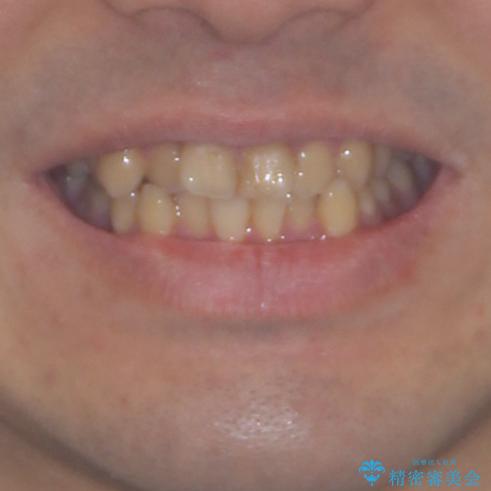

- 上下のデコボコと前歯のクロスバイトを改善したいとのことで来院された患者様です。

マウスピース矯正での自己管理には自信がないとのことで、ワイヤー装置による矯正治療を行うこととしました。

デコボコの程度は強かったのですが、口元の突出感はなかったため、非抜歯矯正としました。